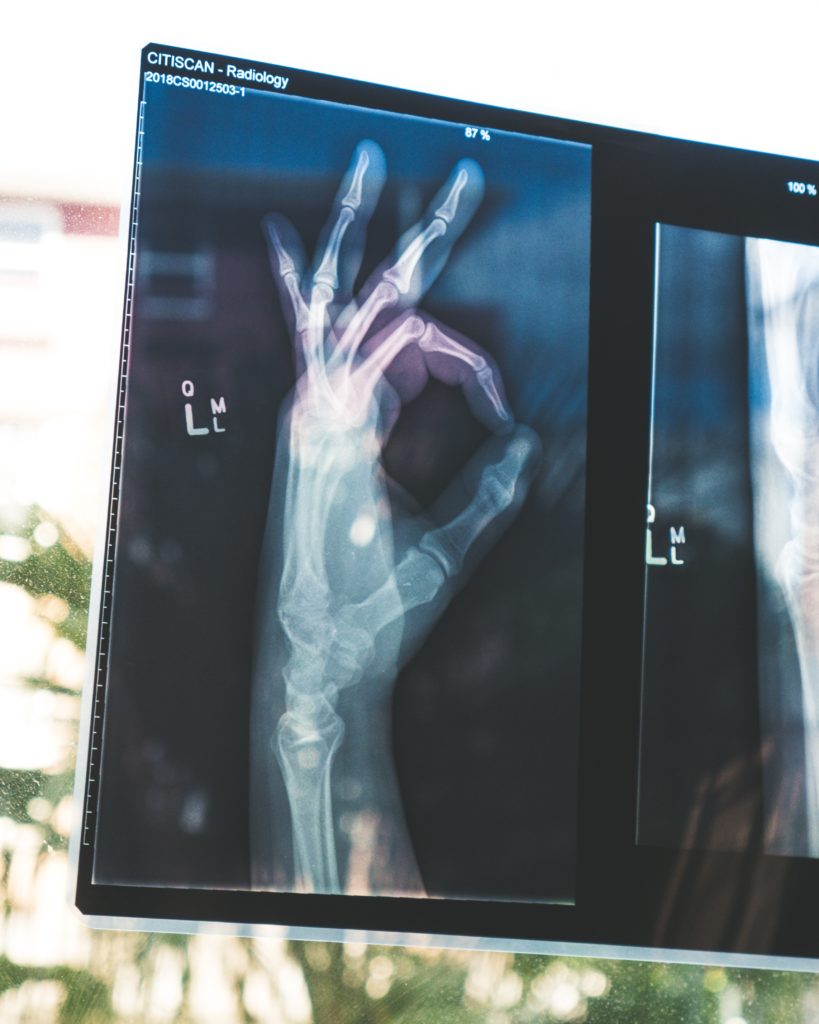

50. Not A Typical X-ray Image

In my whole career as an ER nurse, I've never seen a case like this. One day, a patient came in with abdominal pain. We ran some tests and did an X-ray on his stomach. I went to get the results, and when I saw the X-ray images, my stomach turned upside down. I've never been so disgusted, and I've seen many things! I rushed to find the doctor when my patient was waiting for me, leaned on the door, and said, "Please don't tell my wife." I heard a voice behind me say, "Tell me what exactly?" It was too late. His wife was behind me, and my patient looked like he'd seen a ghost. At the same moment the doctor arrived, and when he saw the X-ray images he almost threw up. The guy has put some kind of bottle inside of him. When his wife asked, "What seems to be the problem?" The doctor calmly replied, "You should talk to your husband." He's going to be in a world of pain after this.

51. Exposed In The Hospital